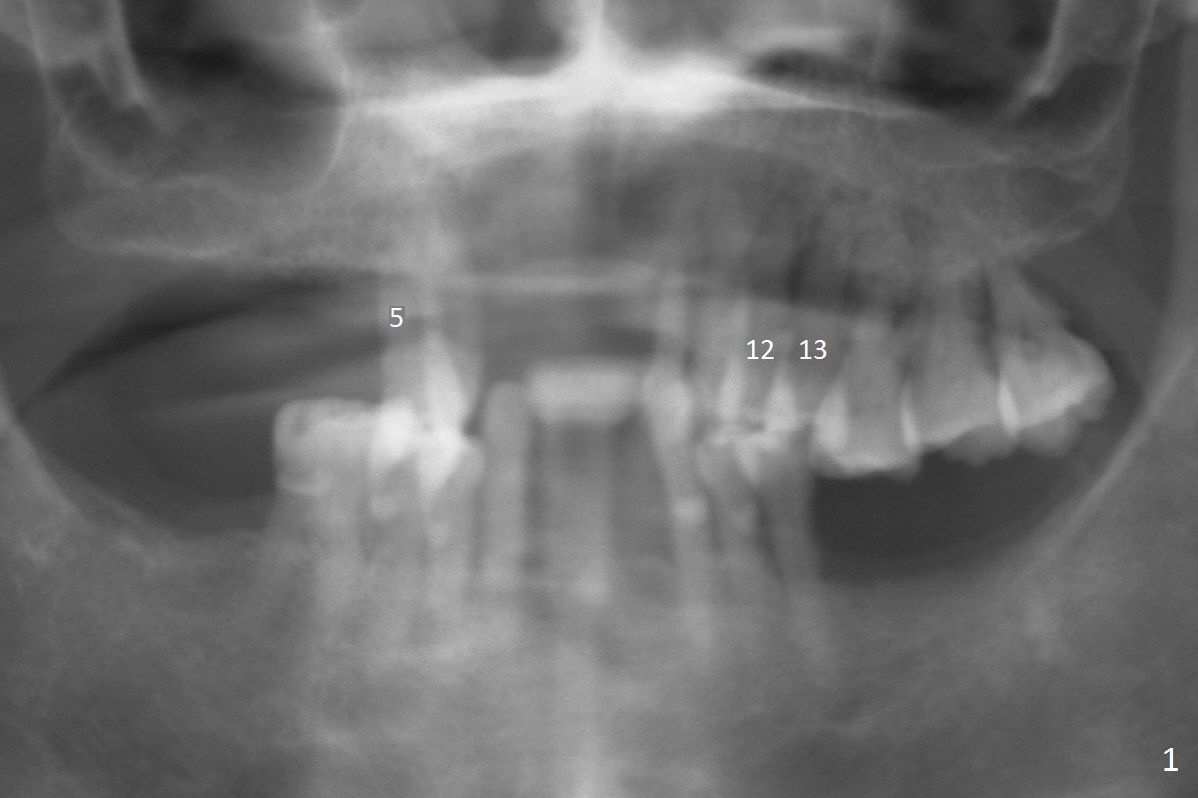

A 65-year-old woman has an upper partial denture and 3 mobile teeth (Fig.1 : #5,12,13). She wants to keep the RPD. The loose teeth are replaced by implants. There is enough bone height (Fig.2). Initial osteotomy depth will be 14 mm. Insert parallel pin(s) and take PA.